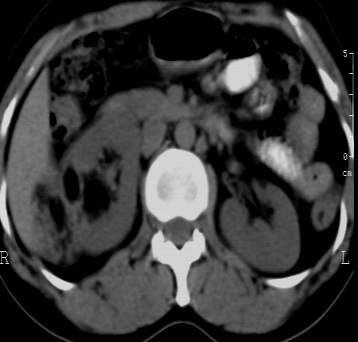

标题: CT24780:女 41岁 右肾多发低密度占位性病灶 [打印本页]

标题: CT24780:女 41岁 右肾多发低密度

女 41岁 超声检查:右肾多发实质性包块,性质待查(提示:错构瘤或其它病变),临床病史不详。

结果收到---右肾细胞癌;单就影像表现是应该首先考虑血管平滑肌脂肪瘤。

病理是有可能搞错不过可能性不大,不过这个确实不能报右肾细胞癌,真难

结果有疑问,什么级别的医院,会不会搞错了

该病理结果应该送高级别医院做病理会诊,否则会影响影像医师今后的判断。免疫组化结果也并未公布,结果非常可疑。应进一步证实。